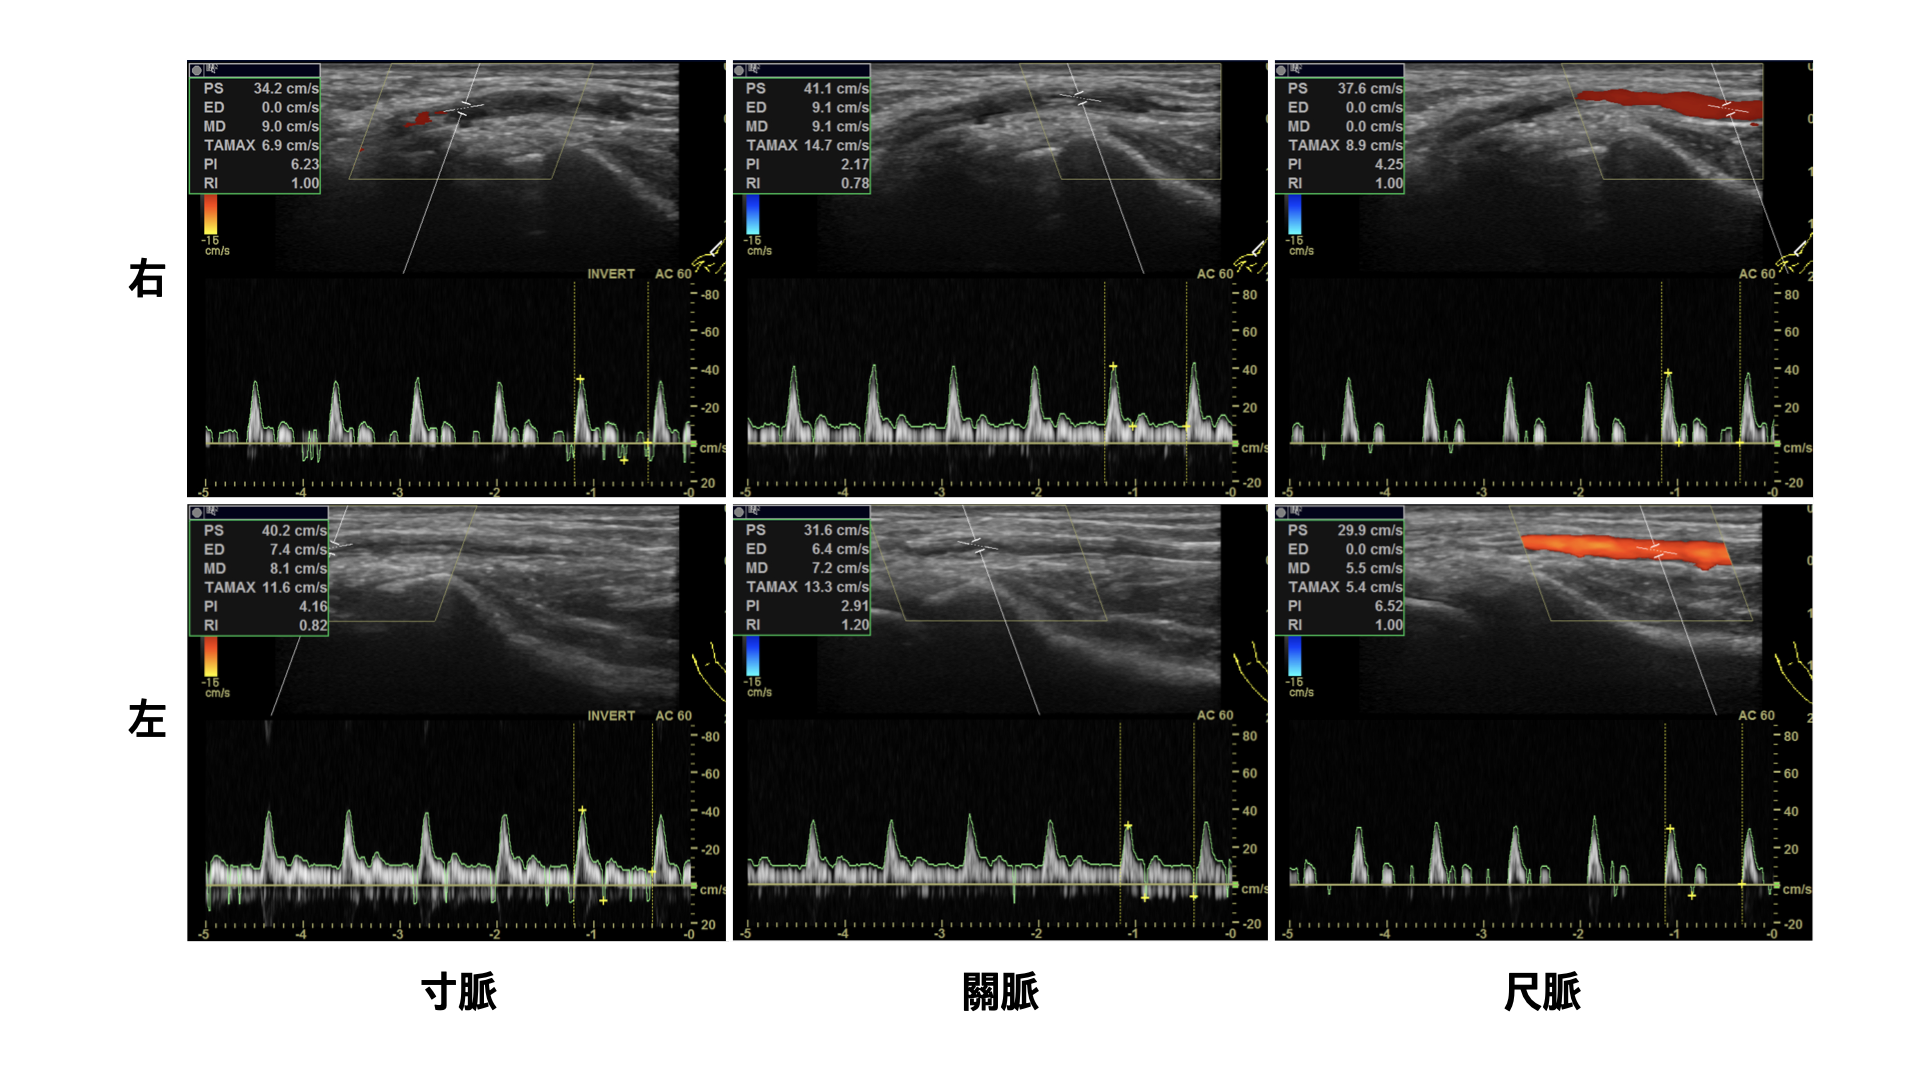

초음파 영상 진단장치를 활용하여 氣口脈(요골동맥)에 대한 脈診을 시행했다(그림2). 脈象이 전체적으로 沈•滑 하였으나, 특히 우측 寸脈•尺脈이 좌측보다 더 沈한 모습을 보였다.

제22화_그림2(불투명).png

그림2. 초음파 영상 진단장치를 활용한 氣口脈(요골동맥) 검사